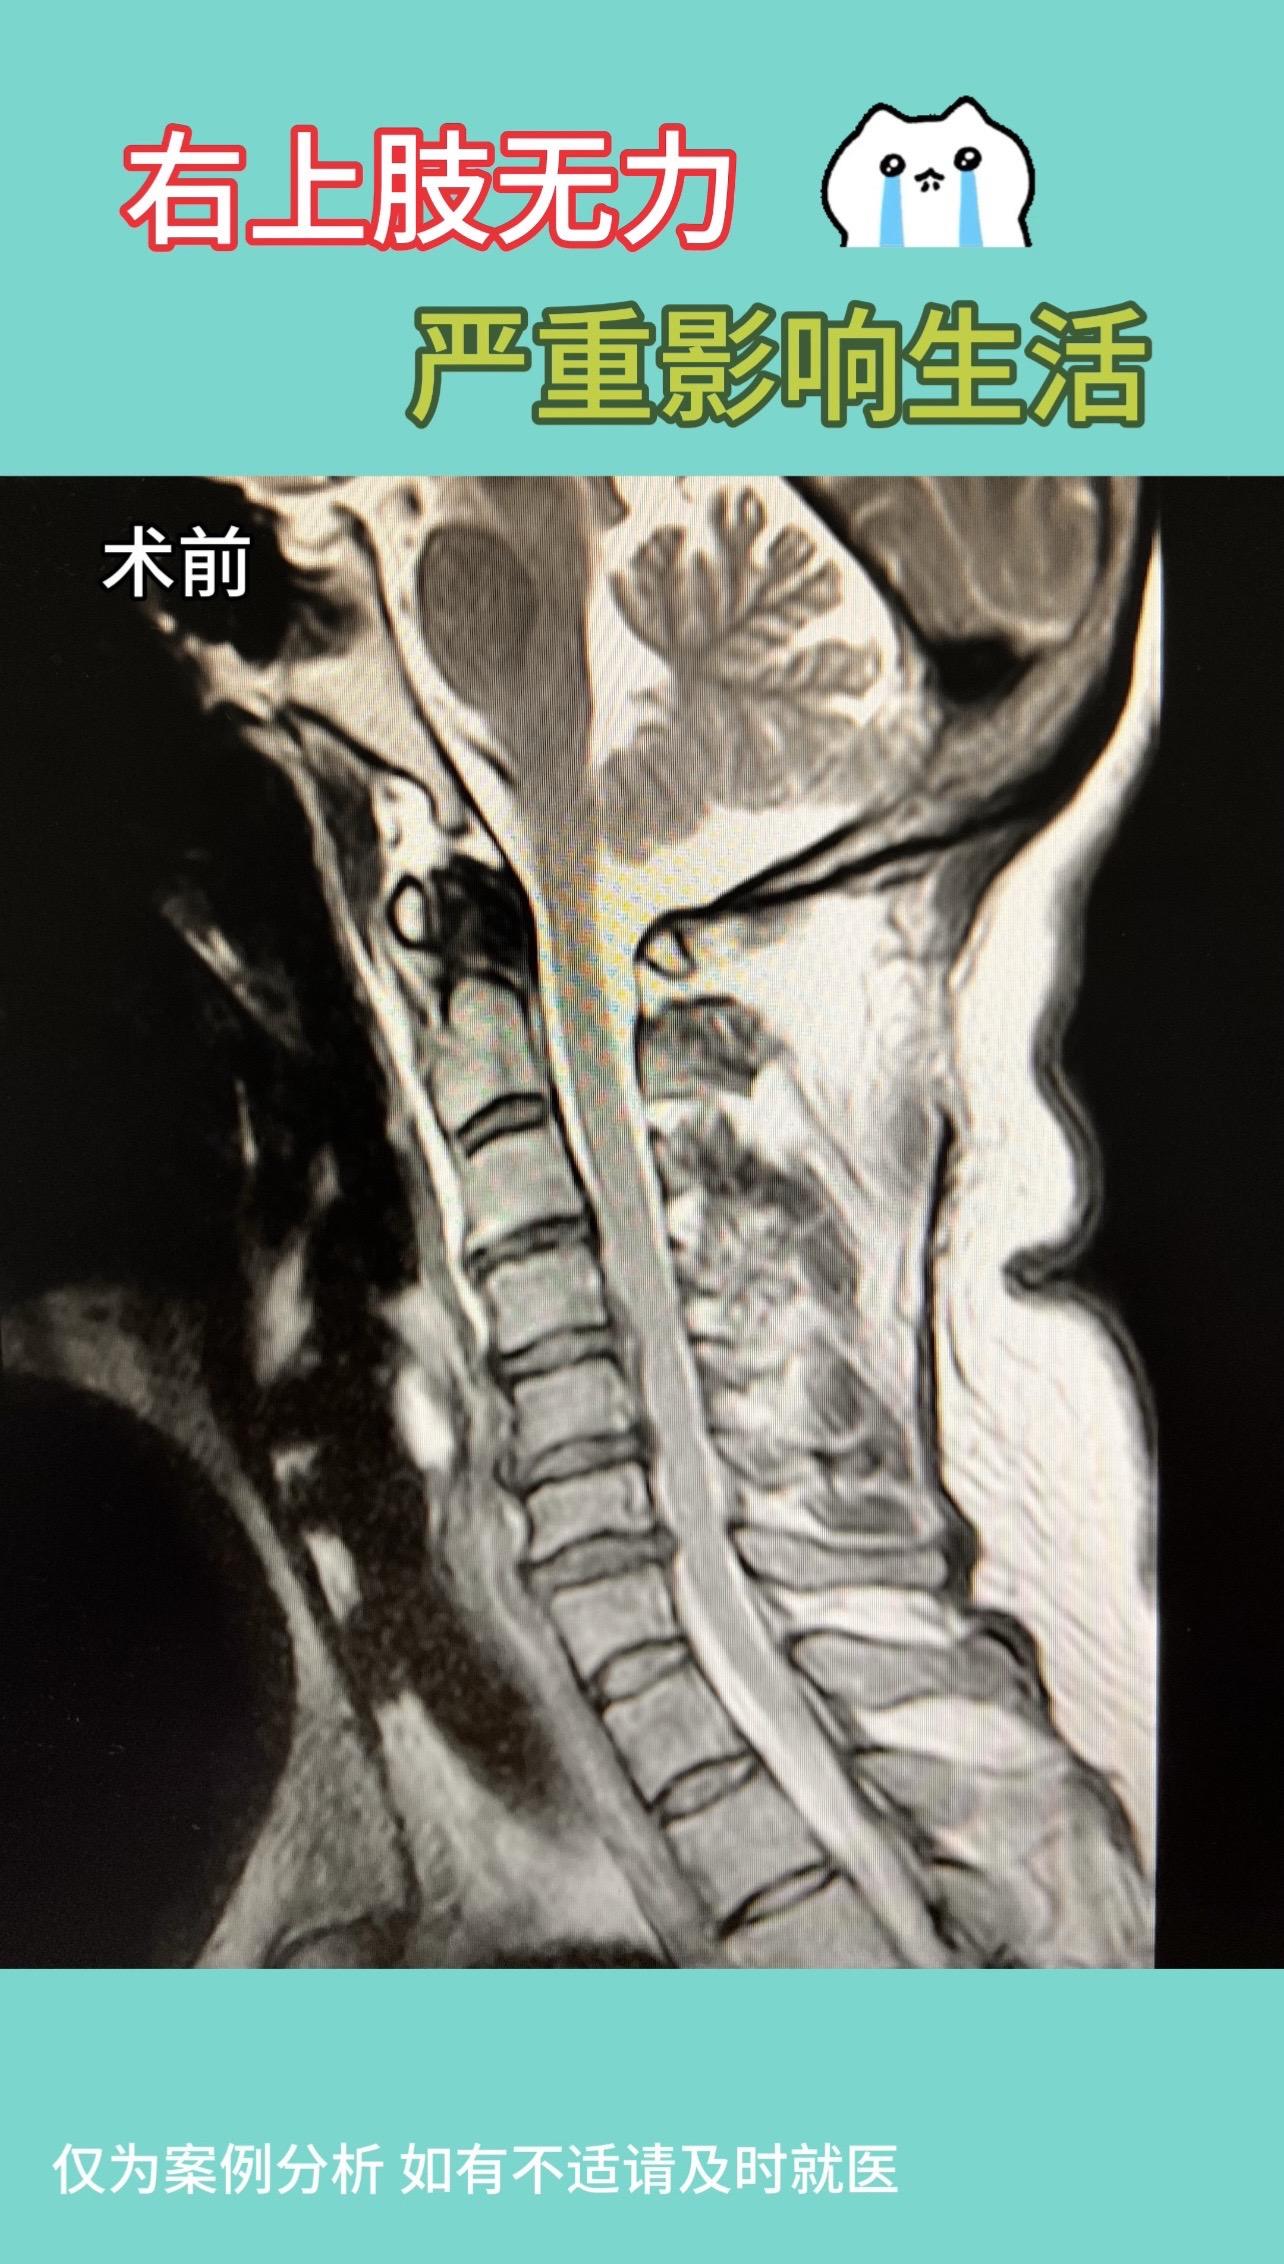

50多岁女性,右上肢无力2月,刷牙不能,持筷不能。严重影响生活。术后1年半,右上肢症状完全消失,颈部伤口愈合好,与皮纹完全重叠,生活中基本看不出来,患者特别满意,也让我们医生充满了成就感。